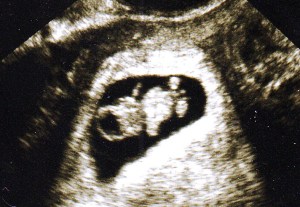

Later that day, I received a phone call assuring me that I was indeed pregnant with my first child. I had blood tests over the course of several days to ensure that my pregnancy hormone levels were doubling. I received my first ultrasound at 6 weeks. I was so thrilled to see its tiny heartbeat on the screen. By my 8-week ultrasound, my child had the small shape of a baby even though it was no bigger than a raspberry.